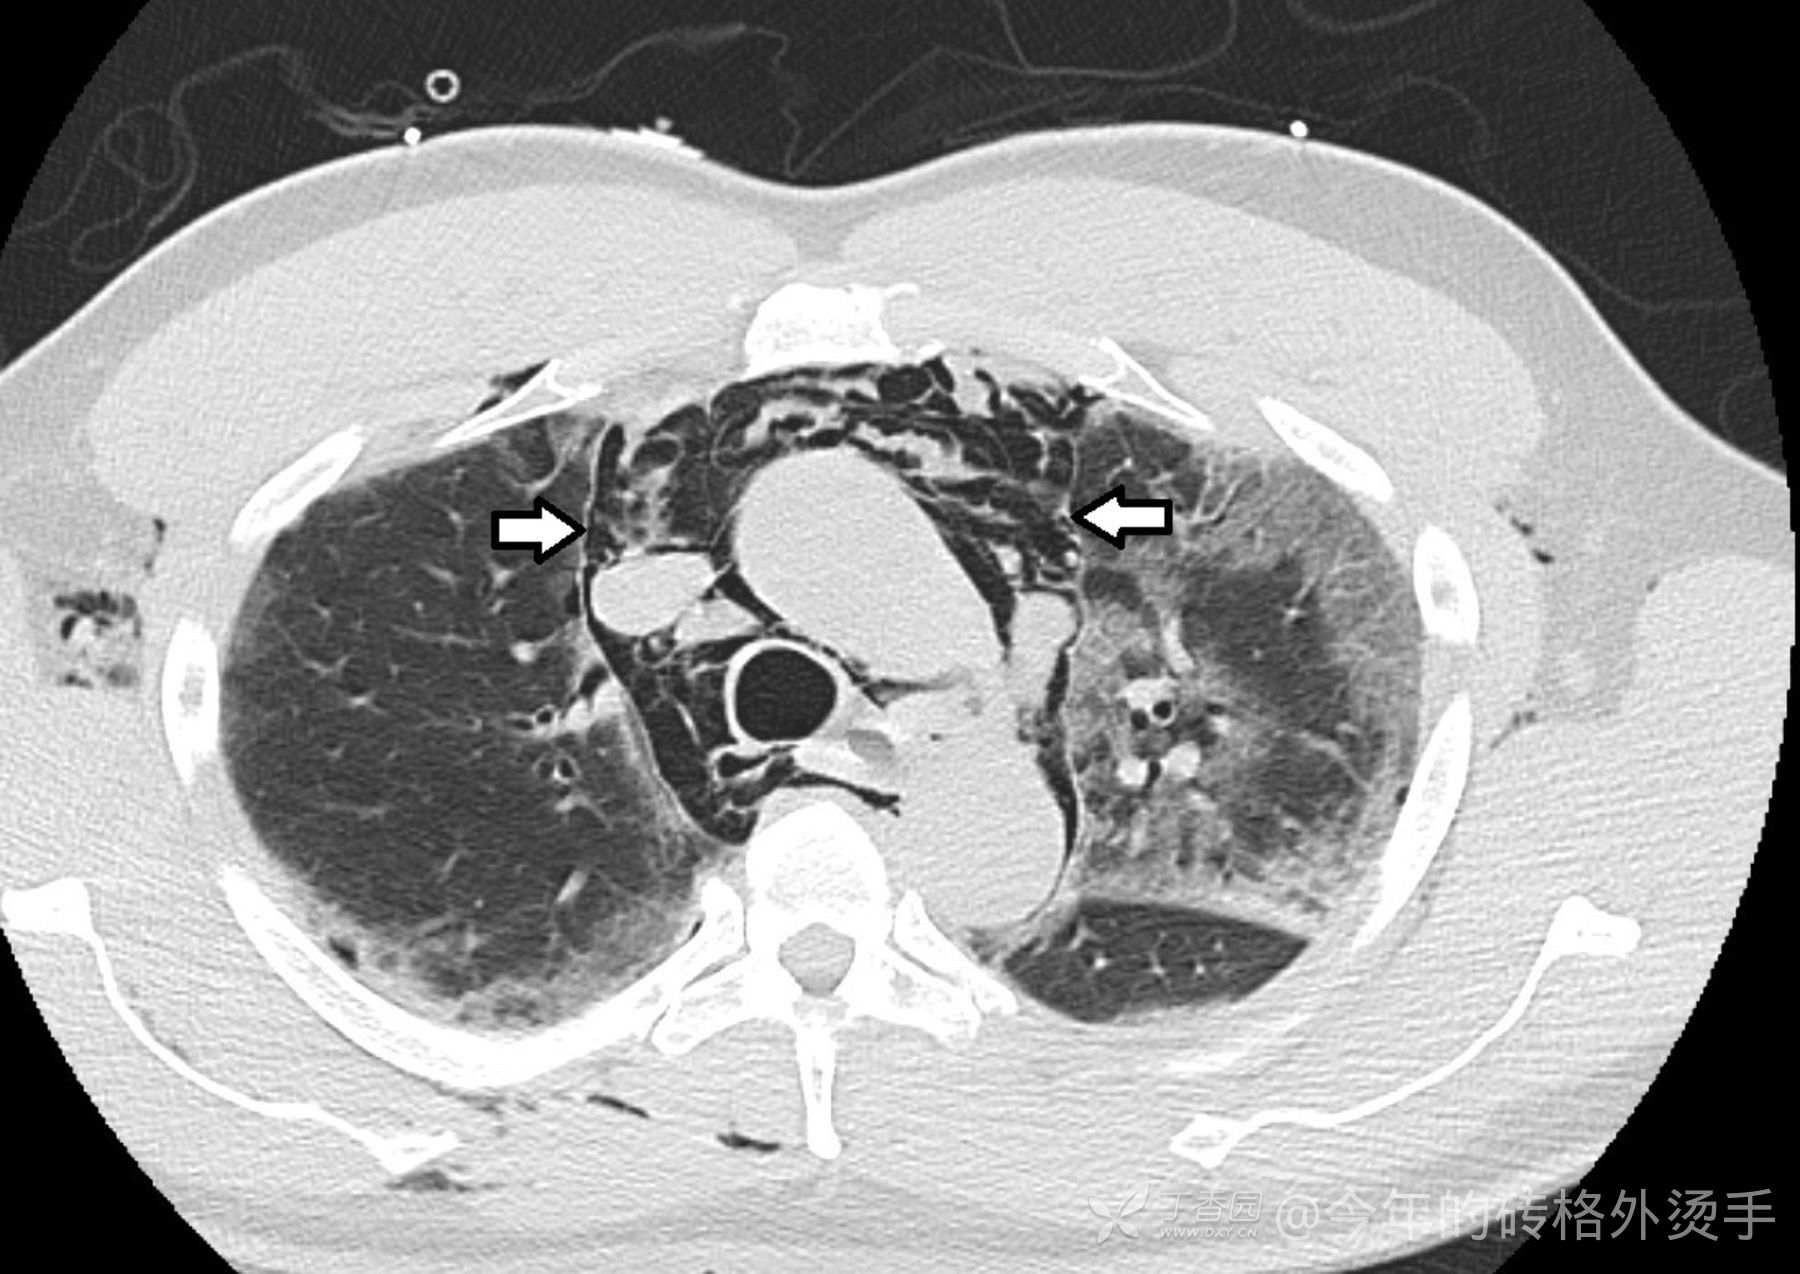

胸部 CT :

住院第 5 天,患者报告突然出现恶心和呕吐,并注意到颈部和胸部周围有捻发音。

复查胸部X光片提示双侧浸润大部分没有变化,但现在上胸腔和可见颈部存在中等软组织气体。

食管造影排除了食管破裂。这个患者既往也无吸烟史、气胸史或其他任何肺部疾病史。

各位站友,有答案了没?气胸?如何鉴别诊断?会不会是新冠导致的并发症?欢迎积极讨论,分享你的真知灼见。